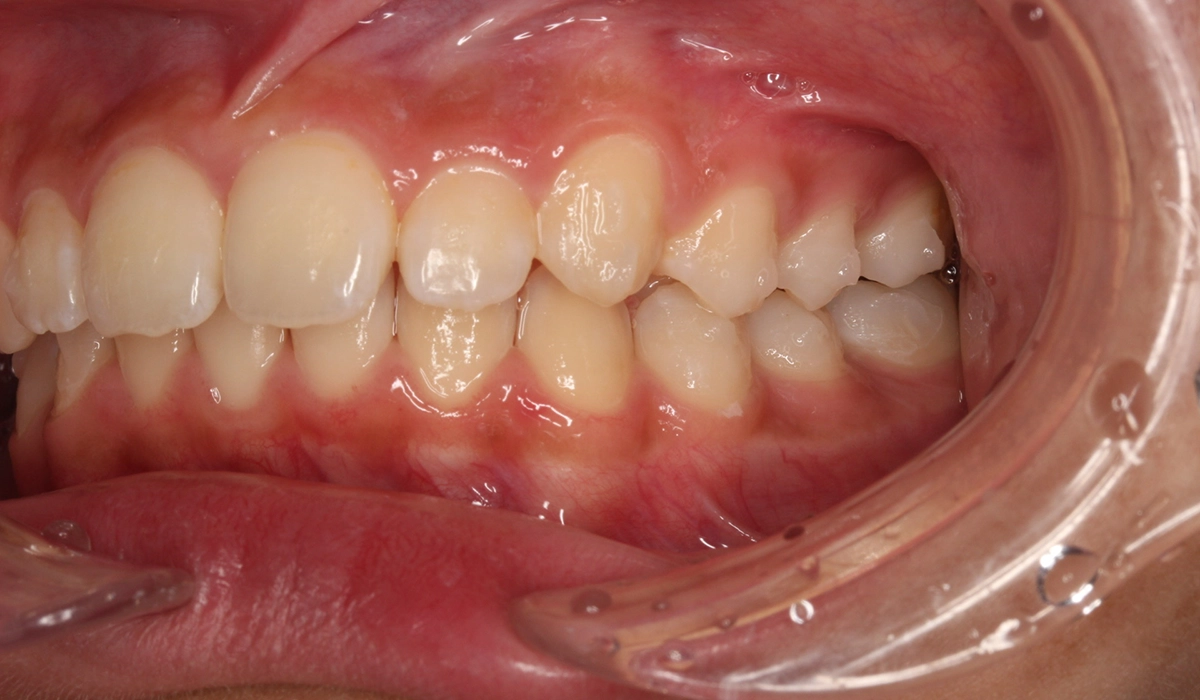

術前:右側

術後:右側